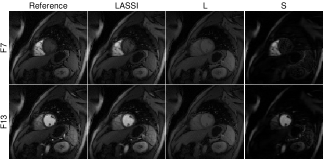

Fig. 3 shows the NRMSE values computed between each reconstructed and reference frame for the LASSI, L+S, and k-t SLR outputs for two datasets. The proposed LASSI scheme clearly outperforms the previous L+S and k-t SLR methods across frames (time). Fig. 4 shows the LASSI reconstructions of some representative frames (the supplement shows more such reconstructions) for each dataset in Tables I-III. The reconstructed frames are visually similar to the reference frames (fully sampled reconstructions) shown. Fig. 4 also shows the reconstruction error maps (i.e., the magnitude of the difference between the magnitudes of the reconstructed and reference frames) for LASSI, L+S, and k-t SLR for the representative frames of each dataset. The error maps for LASSI show fewer artifacts and smaller distortions than the other methods. Results included in the supplement show that LASSI recovers temporal () profiles in the dynamic data with greater fidelity than other methods.

IV-D A Study of Various LASSI Models and Methods